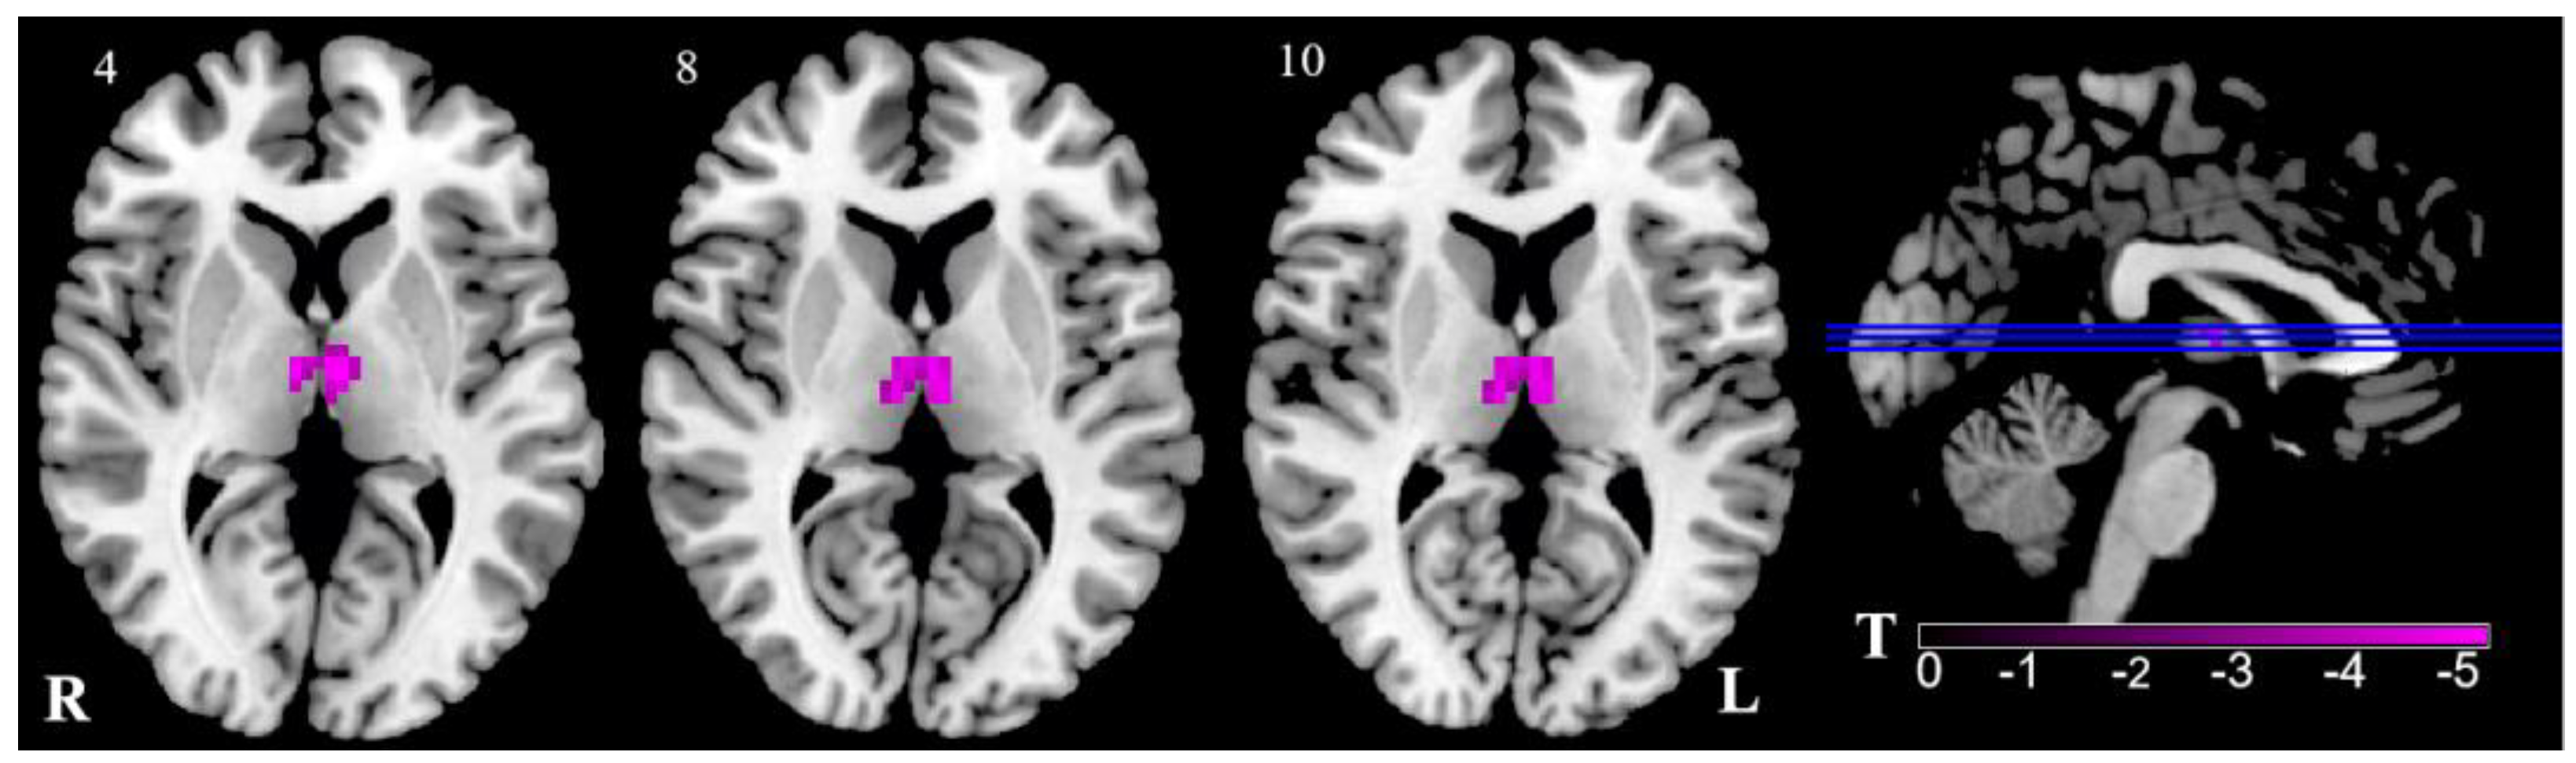

3.2. ALFF Results

| Brain Regions | Peak MNI | Cluster Voxels | T | p | |||

|---|---|---|---|---|---|---|---|

| x | y | z | |||||

| R | Thalamus | 6 | −12 | 6 | 41 | −4.83 | 0.000 |

| L | Thalamus | −3 | −12 | 6 | 43 | −4.83 | 0.000 |